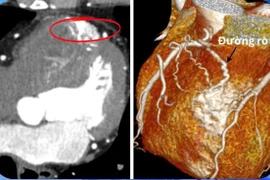

Dò động mạch vành là một tình trạng bất thường trong hệ thống mạch máu tim khiến lượng máu cung cấp cho cơ tim bị giảm, gây ra những triệu chứng như khó thở, đau tức ngực.

Trong lúc đưa con đi khám tại Bệnh viện Nhi đồng Cần Thơ, người phụ nữ 26 tuổi cảm thấy mệt và nhập viện trong tình trạng nguy kịch, khó thở, loạn nhịp thất có biến chứng ngưng tim 10 phút...